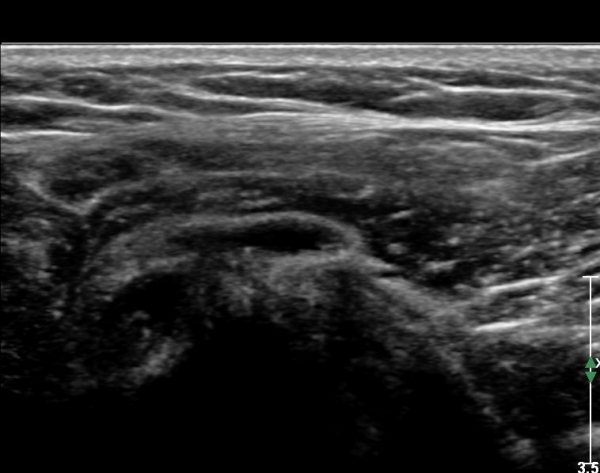

ŽÃËÀÚ¸¦ Á»´õ ¸»´ÜÀ¸·Î À̵¿ ÈÄ(¶Ç´Â ¾Æ·¡·Î ±â¿ïÀÎ ÈÄ) ³»ÃøºÎ¸¦ Á¶ÀýÇÏ´Ï °ß°©ÇÏ±Ù°Ç Ç¥ÃþÀ¸·Î Á¡¾×³¶³» ¼ö¾×Àú·ù°¡ °üÂûµÈ´Ù(»çÁö 3, 4). ŽÃËÀÚ¸¦ Á¶Á¤ÇÏ´Ï ÀÌµÎ¹Ú°Ç ÁÖÀ§ ¼ö¾× Àú·ù¿Í Á¡¾×³¶³» ¼ö¾×Àú·ù°¡ °üÂûµÇ¾î Á¡¾×³¶¿°°ú Ȱ¾×¸·¿°ÀÌ ÀÖÀ½À» ¾Ë ¼ö ÀÖ´Ù(»çÁø 5).

ŽÃËÀÚ¸¦ ¾à°£ ¿ÜÃøÀ¸·Î À̵¿ÇÏ¿© Á¶ÀýÇÏ´Ï À̵ιڰÇÀÌ °üÂûµÇ°í(»çÁø 6) ¾à°£ ¸»´ÜÀ¸·Î À̵¿ÇÏ´Ï °ÇÁÖÀ§ ¼ö¾×Àú·ù°¡ °üÂûµÈ´Ù(»çÁø 7). Á߸³À§¿¡¼ ŽÃËÀÚ¸¦ ¾î±ú ¿ÜÃø¿¡ ´ë°í °ßºÀ°ú ´ë°áÀýÀÌ ¸ðµÎ º¸À̵µ·Ï Á¶ÀýÇÏ¿© ¿ÜÀüÇÏ¸é¼ Ãæµ¹ ¿©ºÎ¸¦ °üÂûÇÑ´Ù. Á¤Áö »óÅ¿¡¼ ´ë°áÀýÀÇ °ñ °á¼ÕÀÌ °üÂûµÇ¾î ¸¸¼ºÀûÀÎ Ãæµ¹À» ½Ã»çÇÑ´Ù(»çÁø 8). ¿ÜÀü½Ã »ó¿Í°ñµÎ°¡ »ó¹æÀ¸·Î ¿òÁ÷ÀÌ°í °ßºÀ°ú Ãæµ¹ÇÔÀÌ °üÂûµÈ´Ù(»çÁø 8, ÷ºÎµ¿¿µ»ó 1).